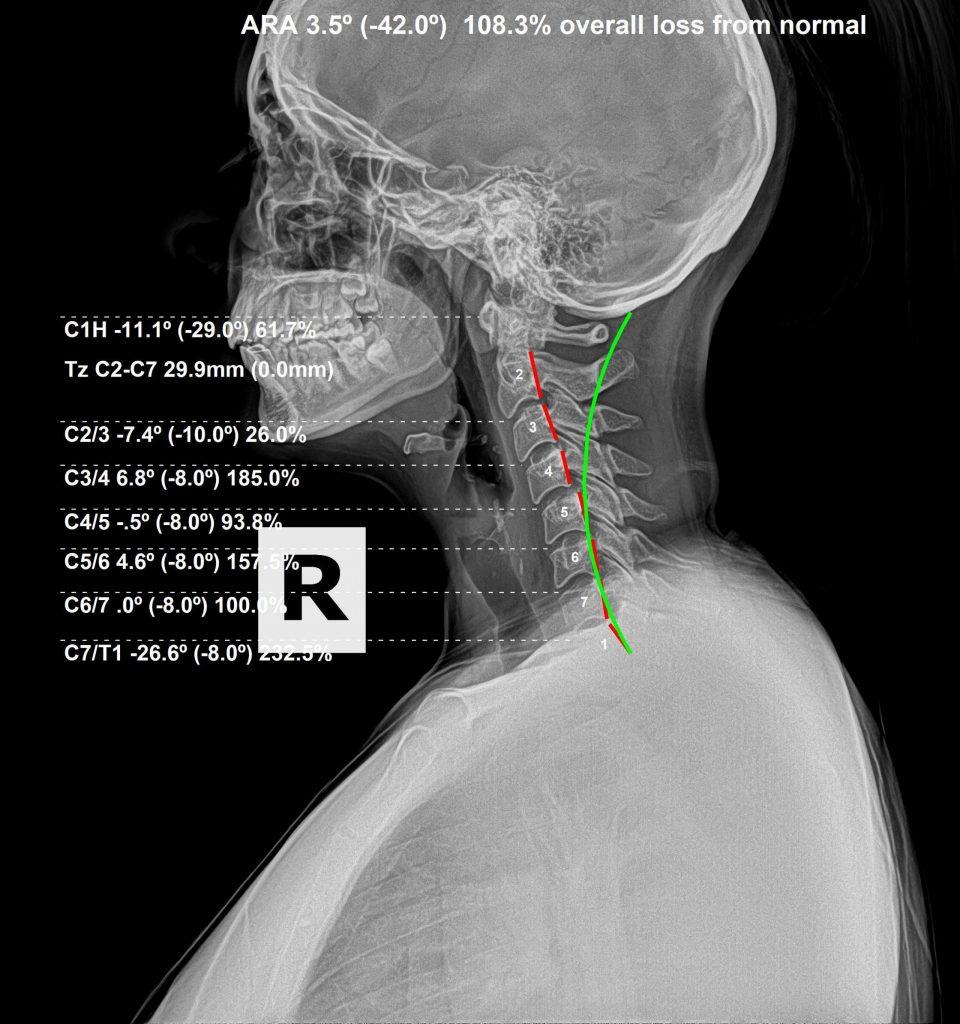

She thought that her symptoms were stemming from the amount of time she spent in front of the computer screen. However, after taking x-rays, we see that she has some pretty significant subluxations in her neck, affecting alignment and stressing her nerve system. Subluxations of the 1st bone of the neck, Atlas, is usually the biggest factor. Loss of the neck curvature (lordosis), is another common factor in people that suffer from these types of symptoms.

When you combine an Atlas subluxation, with a loss of neck curve (lordosis), that puts a tremendous amount of pressure on the spinal cord. The muscles under the skull (sub-occipital muscles) get stretched and will often go into spasm to try and protect the Upper cervical area. This is the perfect storm of stress that affects so many people with headaches / migraines. That is why it is so important to get evaluated and checked as early as possible. This is a correctible and preventable issue.